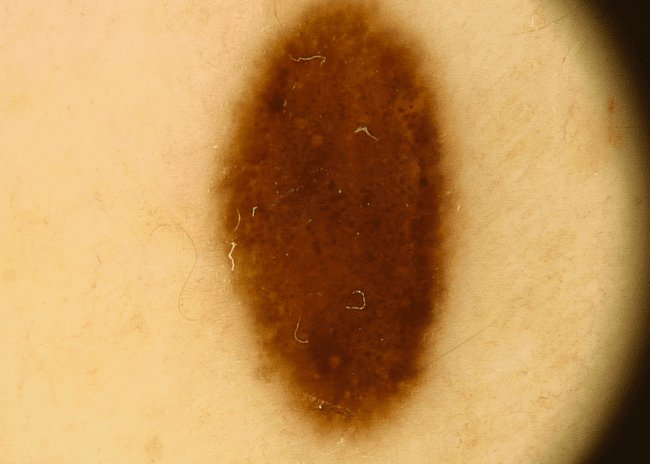

Czerniak złośliwy

Niestety część znamion pod wpływem różnych czynników rakotwórczych (kancerogennych) może przekształcić się w czerniaka skóry. To jeden z najbardziej niebezpiecznych i złośliwych nowotworów. Jego wczesne wykrycie znacznie jednak poprawia rokowania, czerniak wykryty we wczesnym stadium jest praktycznie 100% wyleczalny.

Jak wygląda czerniak?

Dla pacjentów najprostszym sposobem różnicowania pieprzyków jest posługiwanie się kryteriami ABCDE (angielski akronim Asymetry, Border, Color, Diameter, Evolution), które zostały stworzone na Uniwersytecie Nowy Jork 35 lat temu. Kryteria te miały być prostym narzędziem w codziennej praktyce, łatwym do zapamiętania, wzbudzającym czujność zarówno pacjentów jak i lekarzy na cechy kliniczne wczesnego czerniaka. Tak się też stało.

Obejrzyj film i poznaj metodę ABCDE na Instagramie

Opierając się na własnym doświadczeniu w ocenie chorych, członkowie New York University School of Medicine Melanoma Cooperative Group stwierdzili, że asymetria wczesnej postaci czerniaka, nieregularność jej brzegów oraz różnorodność barw były ściśle związane z przekraczaniem przez nią średnicy 6 mm. Co nie zmienia faktu, że ta metoda pozwala wykryć i zróżnicować nieco mniejsze i wcześniejsze pod względem zaawansowania postaci czerniaka.

Reasumując każdy pieprzyk o asymetrycznych kształtach, nierównych brzegach, zmieniający kolor i/lub średnicę, nabrzmiały, podrażniony, krwawiący wymaga natychmiastowej konsultacji z lekarzem specjalistą i wykonania badania dermatoskopowego.

Nie ma jednego wzorca czerniaka dlatego różnicowanie ze zwykłymi znamionami bywa trudne nawet dla specjalistów w tej dziedzinie. W diagnostyce dermatologicznej do każdego przypadku podchodzi się indywidualnie.

Niestety znamiona mogą do złudzenia przypominać czerniaki, więc odróżnienie zwykłego pieprzyka od typowego czerniaka może być trudne. Znamiona atypowe – dysplastyczne mogą imitować czerniaki, a niektóre czerniaki bardzo przypominają znamiona i dopiero usunięcie zmiany i badanie histopatologiczne pozwalają na postawienie trafnej diagnozy.